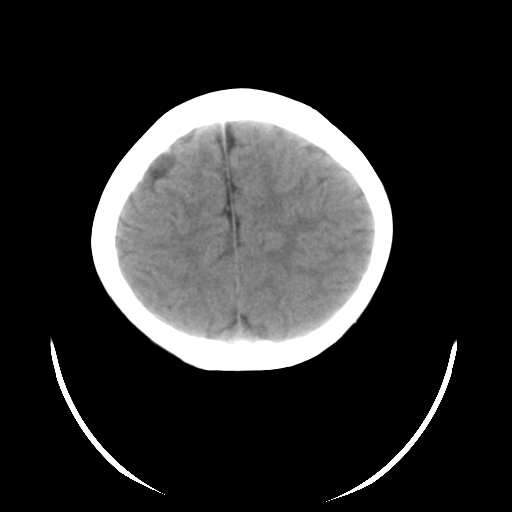

标题: PED3080:女,6岁,头痛、呕吐一天。 [打印本页]

女,6岁,头痛、呕吐一天。

颅脑ct平扫未见明显异常。

头颅ct平扫未见明确异常,随诊复查。